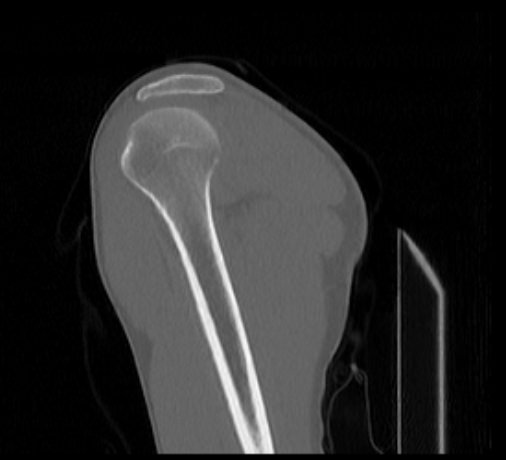

Мультиспиральная компьютерная томография является наилучшим методом диагностики патологии костной ткани и применяется для выявления различных патологических процессов в области плечевой кости.

Методика КТ построена на использовании ионизирующего излучения, которое в разной степени поглощается органами и тканями человека. Рентгеновские лучи лучше всего поглощаются костными структурами, поэтому на послойных изображениях, полученных при КТ-сканировании, хорошо видна плотность и внутреннее строение плечевой кости, а также плечевого и локтевого суставов. При этом визуализируются костные повреждения, очаги деструкции, воспалительные изменения.

Что показывает КТ плечевой кости

- повреждения костей в результате полученной травмы – трещины, переломы, смещения.